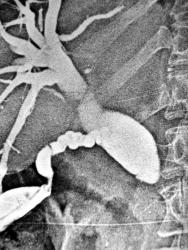

Да очень похоже на рак терминального отдела холедоха. Для наглядности пример из нашего архива начала 80-х годов (отсутствие приличных УЗИ и КТ). Рак терминального отдела холедоха с верификацией после операции (такие опухоли можно оперировать, в отличие от рака головки ПЖ, где исход при похожей картине будет не очень хорошим).

На первой ангиограмме- целиакография после введения 10 мкг адреналина(фарм проба) - сегментарные артерии печени спазмируются, в проекции терминального отдела холедоха увеличенные артерии(передние панкреато-дуоденальные), которые снабжают опухоль (стрелка). На втором снимке сочетанная чрескожная чреспеченочная холангиография (через иглу Шиба 0.7 мм диаметром) и целиакография- виден дефект наполнения в терминальном отделе, расширение холедоха и желчного пузыря.

Сдавление холедоха извне, черное пятно - желчный пузырь раздутый воздухом в ортоградной проекции.

Холедох "пломбированный" конкрементами